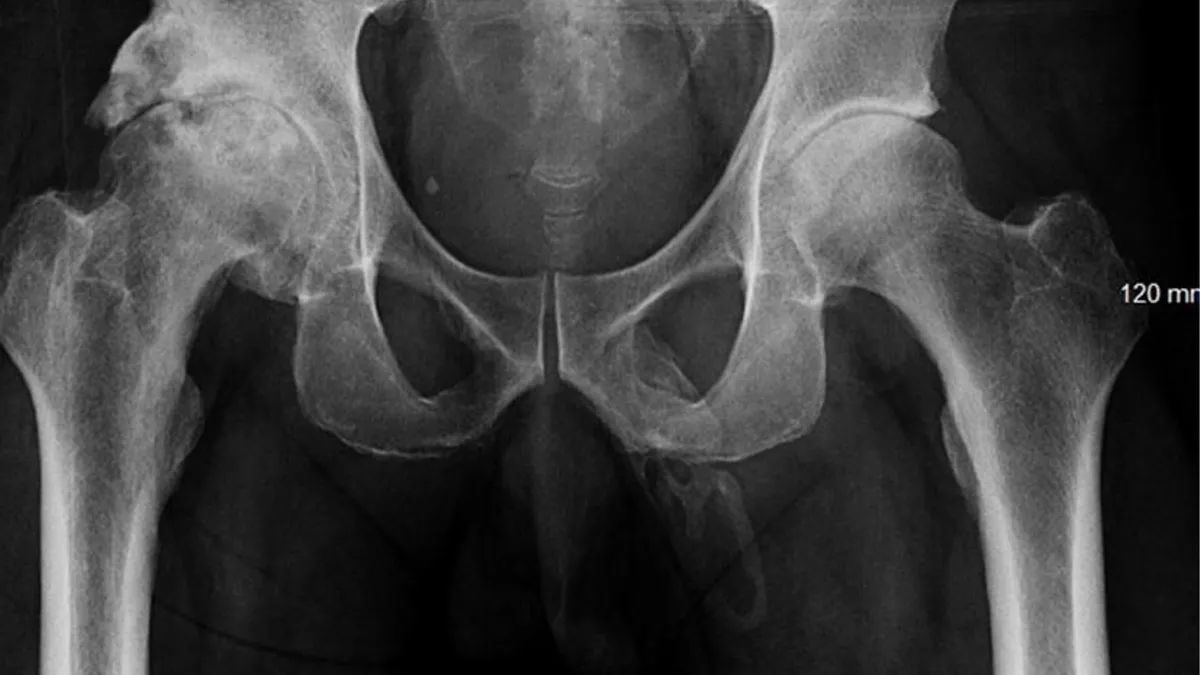

Когда врачи исследовали потенциальную причину боли, они не обнаружили ни одного отека предстательной железы и прочего. Они сделали рентген таза, чтобы выявить переломы. В свою очередь они обнаружили костный нарост в неожиданном месте – в пенисе мужчины.

Врачи диагностировали у пациента окостенение полового члена, при котором внутри него образуется костная внескелетная структура. Это происходит из-за накопления солей кальция в мягких тканях органа.